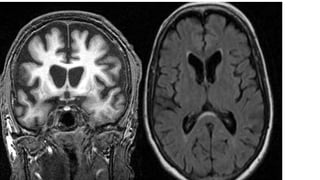

3. Coronal sequences

•hippocampal, choroidal fissure and temporal horn size

•symmetry

• left > right atrophy favours FTLD

• equal involvement favours Alzheimer's disease

•anterior to posterior gradient

• anterior atrophy > posterior atrophy favours FTLD

•involvement of the temporal lobe generally favours FTLD

•atrophy largely restricted to the hippocampus and parahippocampal

gyrus favours Alzheimer's disease

•mammillary body size, signal and symmetry

MEDIAL TEMPORAL LOBE ATROPHY

SCORE

visual score performed on MRI of the brain using coronal T1 weighted images through the

hippocampus at the level of the anterior pons and assesses three features

width of the choroid fissure

width of the temporal horn of the lateral ventricle

height of the hippocampus

These result in a score of 0 to 4.

0 = no CSF is visible around the hippocampus

1 = choroid fissure is slightly widened

2 = moderate widening of the choroid fissure, mild enlargement of the temporal horn and

mild loss of hippocampal height

3 = marked widening of the choroid fissure, moderate enlargement of the temporal horn,

and moderate loss of hippocampal height

4 = marked widening of the choroid fissure, marked enlargement of the temporal horn,

and the hippocampus is markedly atrophied and internal structure is lost

In a patient younger than 75 years of age, a score of 2 or more is abnormal.

In a patient 75 years or older, a score of 3 or more is abnormal.